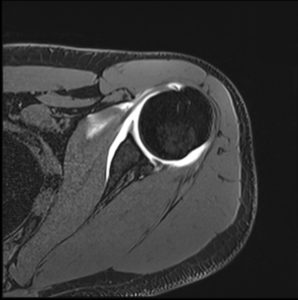

Une arthro-IRM peut être réalisée. Elle nécessite préalablement une injection d’un produit de contraste dans l’articulation en salle conventionnelle de radiographie. Immédiatement après l’IRM de l’articulation est réalisée. Comme pour toute ponction, il y a un risque très faible d’infection bien que toutes les précautions nécessaires pour l’éviter aient été prises. Dans ce cas il faut appeler le radiologue ou votre médecin prescripteur sans délai si votre articulation présente des symptômes inhabituels à type de douleurs, gonflement, s’il apparaît de la fièvre dans les jours qui suivent l’examen. Limitez les mouvements de votre articulation durant les 24 heures suivantes pour éviter la survenue de douleurs ou d’un épanchement (gonflement). Interrompez le sport et la kinésithérapie pendant 48 heures et 4 à 5 jours si une infiltration de cortisone a eu lieu.